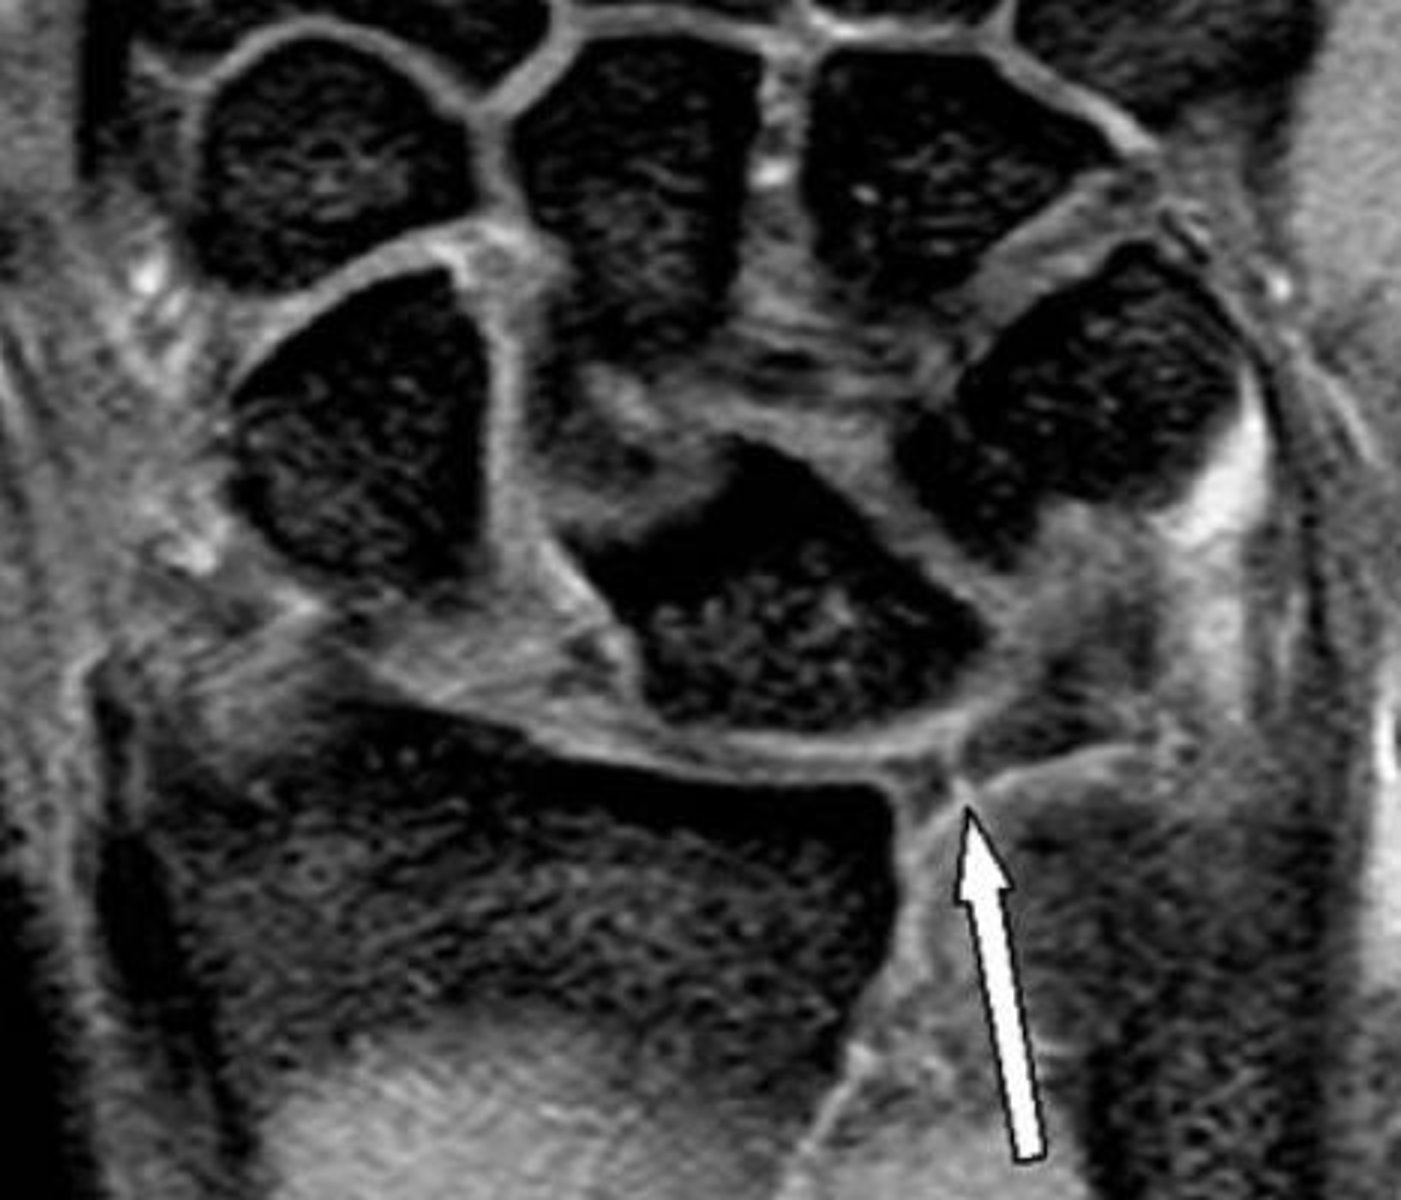

Scapholunate (SL) dissociation

FOOSH resulting in SL ligament tear

Lunate follows triquetrum into extension

Capitate collapses into the empty space between the scaphoid and lunate

Scapholunate advanced collapse (SLAC) wrist \

Results in dorsally displaced lunate